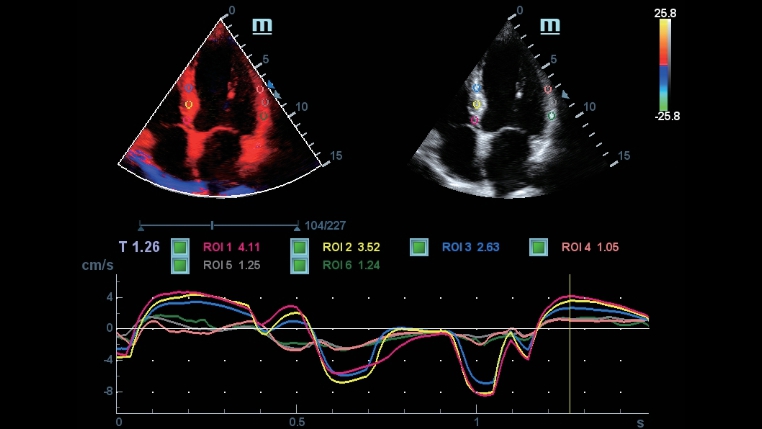

??? ???

??/??? ? ?? ???????? ???? ??? ??? ???? ?????? ??? ??? ?? ??? ??? ???? ?????.